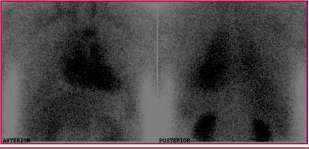

Debido a los hallazgos de la resonancia magnética, se solicitó una gammagrafía miocárdica con 99 mtic-piro-fosfato/SPECT. Se adquirieron imágenes a los 60 y 180 minutos posinyección, de cuerpo entero en proyecciones anterior y posterior, y selectivas de la región cardíaca (anterior, oblicua anterior izquierda y lateral izquierda).

A los 180 minutos también se obtuvieron imágenes cardíacas en modo SPECT. En las imágenes de 60 y 180 minutos posinyección planares y SPECT, se observó una captación aumentada y difusa del trazador en el miocardio, compatible con amiloidosis TTR (hereditaria o senil) (Figura 2). (3)